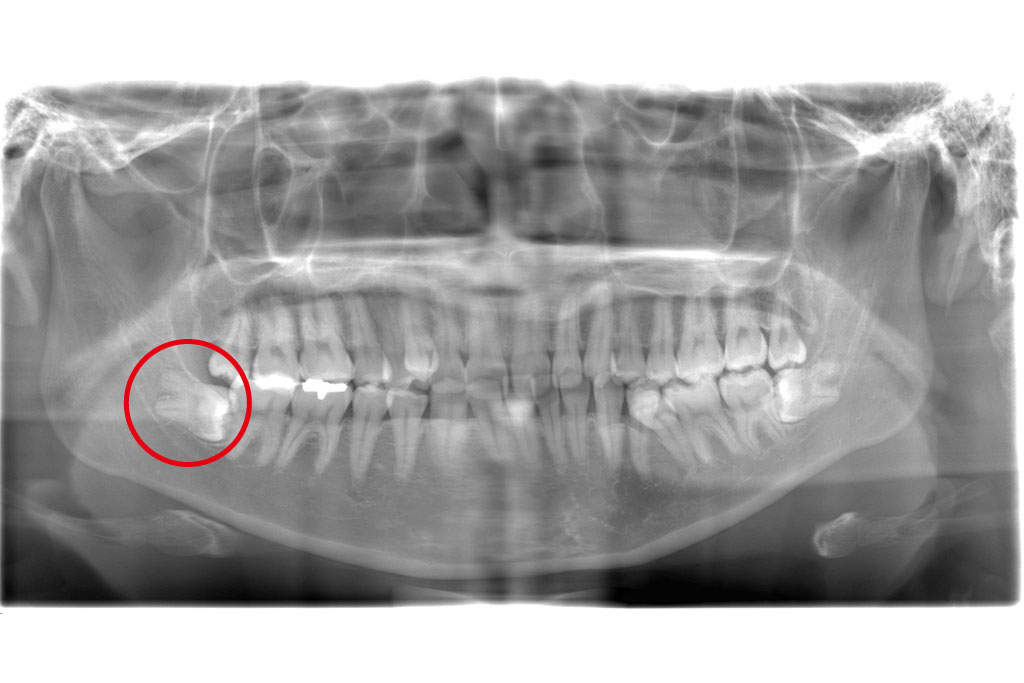

父のレントゲン写真と口腔内を見て、インプラントを入れる位置を一緒に決めて行きました。

右上は歯があるように見えて隣の歯につなげてある被せ物があるだけの状態です。

その右上は骨がないためサイナスリフトという処置を施した後にインプラントを入れる手術をしなければならないのですが、(サイナスリフトは骨を作るだけで6ヶ月待ちます。)

私は水口先生が開発したオステオプッシャーを用いて、骨がないところに骨を足す手術と並行してインプラントを入れる手術を施しました。

左側の入れ歯を入れていたと言っている場所には通常の方法でインプラント治療を、左上の奥歯2本は歯周病でグラグラだったため抜歯と同時にインプラントと治療を行いました。

左側のレントゲンがが最初の状態です。右側がインプラントを入れ、被せ物まで入れた状態のレントゲンです。